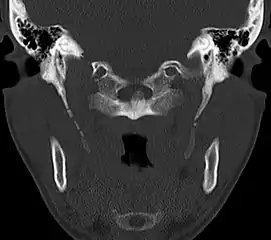

In vascular Eagle syndrome, the elongated styloid process comes in contact with the internal carotid artery below the skull. In these cases, turning the head can cause compression of the artery or a tear inside the blood vessel, which restricts blood flow and can potentially lead to a transient ischemic attack or stroke.[5] Sometimes, compression of the internal jugular vein can also occur and might lead to increased intracranial pressure.[7][8][9]

Eagle syndrome occurs due to elongation of the styloid process or calcification of the stylohyoid ligament, potentially compressing the nearby carotid arteryor glossopharyngeal nerve.[4] However, the cause of the elongation hasn’t been known clearly. It could occur spontaneously or could arise since birth. Usually normal stylohyoid process is 2.5–3 cm in length, if the length is longer than 3 cm, it is classified as an elongated stylohyoid process.[10] There are reports of eagles syndrome been elicited after wisdom tooth removal. [11]

Imaging is important and is diagnostic. Visualizing the styloid process on a CT scan with 3D reconstruction is the suggested imaging technique.[12] The enlarged styloid may be visible on an orthopantogram or a lateral soft tissue X ray of the neck.